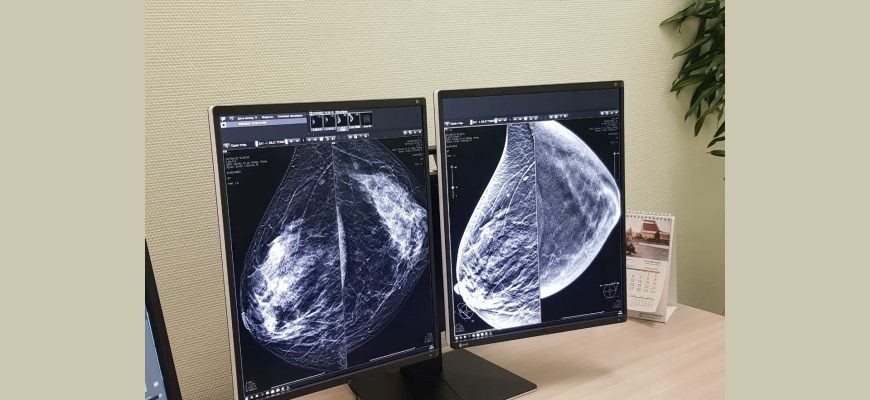

Искусственный Интеллект и МРТ: Как Мы Научили Машину Видеть Больше, Чем Глаз В мире, где технологии развиваются с невероятной скоростью, мы, как энтузиасты